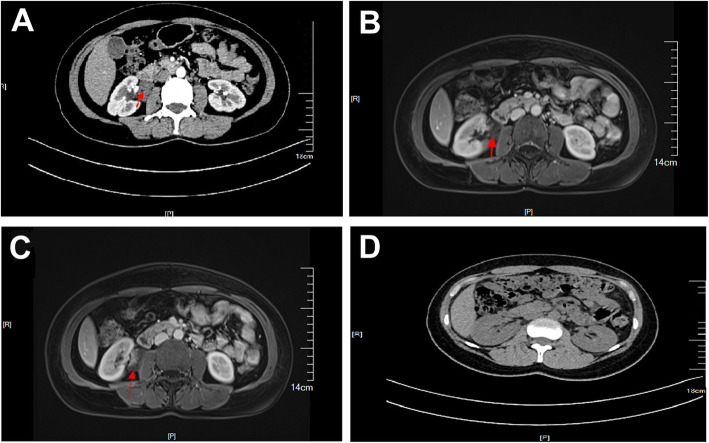

A 46-year-old woman of Han nationality, who had a history of appendectomy 2 months ago, was admitted to hospital again on April 1, 2019, due to had a pain on the right side of the waist for more than 20 days. Physical examination showed no abnormities in head, chest, abdomen and limb activity. There was no mass in the right kidney and the patient felt pain when tapping on her kidney. Routine blood test showed that the number of erythrocyte and leukocyte were 3.7 × 1012/L and 7.37 × 109/L, respectively, and the level of hemoglobin was 108 g/L. Urine routine test showed that erythrocyte and leukocyte were 44.7/ul and 361.2/ul, respectively. Computerized tomography (CT) revealed an ill-defined soft tissue mass on the junction regions of ureters and right renal pelvis, the lesion were obviously continuously and unevenly enhanced and with calcified margins, and enlarged hydronephrotic right renal pelvis (Fig. 1a). Magnetic resonance imaging (MRI) showed the ill-defined soft tissue mass of a size of 3.1 cm × 2.3 cm × 4.0 cm with an unclear margin (Fig. 1b). Enhancement scan showed significant and continuous uneven mass, limited diffusion weighted imaging (DWI), high signal intensity on apparent diffusion coefficient (ADC) map, the lesion had unclear margin with right renal collecting system, the right renal pelvis and partly ureter moved to forward, and enlarged hydronephrotic right renal pelvis (Fig. 1c). Other examinations, including electrocardiogram (ECG), chest film, biochemistry analysis, coagulation, blood cortisol, vanillylmandelic acid (VMA), renin activity, angiotensin I, angiotensin II, epinephrine and noradrenaline, were all normal. Preliminary diagnosis was therefore right parapelvic mass.

Fig. 1.

a The CT image of cavernous hemangioma; b The MRI image of cavernous hemangioma; c The enhancement scan image of the cavernous hemangioma; d The CT image of the patient after discharging 3 months

On April 16, 2019, after general anesthesia, the patient was placed in the left lateral position and performed DaVinci robotic-assisted laparoscopic resection of parapelvic lesion via the transabdominal approach. A small incision about 1 cm was made at the umbilical margin of the affected side with a Veress needle to establish pneumoperitoneum at pressure of 12–15 mmHg. Then, a 12 mm-Trocar was inserted into abdominal cavity through the incision (Fig. 2). Two mechanical arms were located at a distance of 8–10 cm to the lens hole to control various instruments: the mechanical arm 1 (8 mm) was 2–3 cm to the twelfth rib; the mechanical arm 2 (8 mm) was on 15 ° angle and 2–3 cm medial to the anterior superior iliac spine. Auxiliary holes A and B were established 5 cm outside the midpoint of the connection between the camera arm and mechanical arm 1 and 2, respectively. Due to the right side lesion, a 5 mm-Trocar was placed under the xiphoid process to lift the liver in auxiliary hole C. The next measures were to loosen the adhesion in the abdominal cavity, dissect the parietal peritoneum along the paracolic sulcus, push the ascending colon to the opposite side, dissect the ligament of the liver and colon, insert the needle holder with the self-locking device into the auxiliary hole C under the xiphoid, and lift the lower edge of the liver. The electric scissors was used to sharply separate the anatomical space between the inferior vena cava and the duodenal descending fusion fascia. After pushing the duodenum to the medial side, perirenal fascia and the tissue on the surface of the renal pelvis were opened, and the upper ureter was separated along renal pelvis. Purple/brown hemangioma-like neoplasm with a diameter of about 4 cm was observed in the upper segment of the right ureter and behind the right renal pelvis, it surrounded the junction of right renal pelvis and ureter, and its blood supply originated from the vessels in the right renal sinus (Fig. 3a). The cavernous hemangioma was completely removed through DaVinci robotic-assisted laparoscopic resection following the steps in the video (see Supplementary Video, Fig. 3b). The surgery is uneventful and the patient was followed up until now without any complications (Fig. 1d).